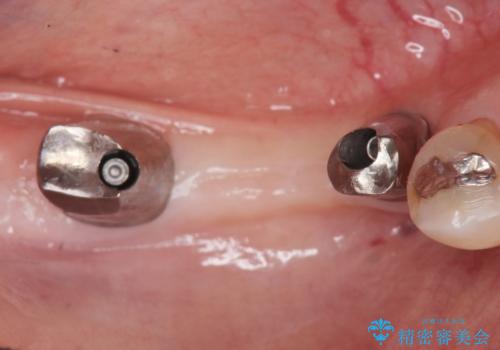

なるべく予算を抑えたいとのご希望から、上顎は入れ歯、右下臼歯部はインプラントによる治療を行いました。

インプラントの種類:スプラインツイスト